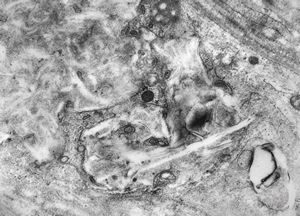

F,49y. | purulent meningitis- meningococcal v.s.

F,49y. | purulent meningitis- meningococcal v.s.

F,49y. | purulent meningitis- meningococcal v.s.